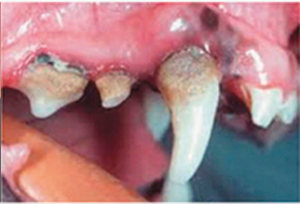

第三階段:中期齒根骨膜炎第四階段:晚期齒根骨膜炎---慢性細菌感染持續摧毀牙齦、牙齒和骨質。細菌通過血液蔓延到身體各處,可損壞腎、肝和心臟。

第四階段:晚期齒根骨膜炎• 口腔問題四:嚴重的牙周病會影響愛寵的健康甚至是壽命。

如果不及時治療,牙周疾病除了帶給寵物痛苦,牙結石中的細菌會通過口腔傷口進入愛寵的血液中,循環到身體各個重要器官,引起多種併發症,如細菌性心內膜炎、肝炎、腎盂腎炎等,嚴重時,甚至會危及生命!